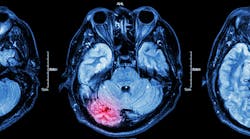

Inflammation, or swelling, is the body’s natural response to infection. It is possible that as oral bacteria travel through the body it triggers a similar response, which then leads to the formation of arterial plaque. (6) Oral bacteria have been found in the fatty deposits of people with atherosclerosis. (7) These deposits can narrow arteries or break loose and clog them entirely, leading to heart attack or stroke.